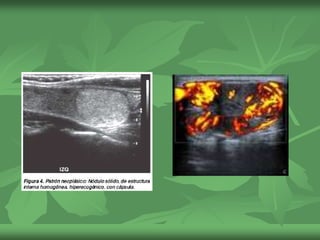

ADENOMA

 NEOPLASIAS VERDADERAS CON

CAPSULA FIBROSA Y COMPRESION DEL

TEJIDO ADYACENTE

 Indistinguible del carcinoma, solo por

histologia

 Solidos de disfentes ecogenicidad, con halo

grueso pero liso, que corresponden a

estructuras vasculares que se dirigen hacia las

regiones centrales.

Doppler color:

muchos estudios demostraron que los nódulos

neoplásicos (adenomas o carcinomas) presentan flujo

intranodular, mientras que los nódulos coloides son

avasculares con patrón de flujo periférico.